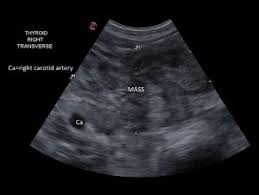

Cancer In Dogs Signs Diagnosis And Treatment Bechewy from media-be.chewy.com What sets srs apart is its unprecedented precision, which enables the. What is thyroid cancer (adenocarcinoma) in dogs? Whether you or someone you love has cancer, knowing what to expect can help you cope. When cancer starts in the thyroid gland, it is called thyroid cancer. The thyroid glands are paired structures located along the windpipe (trachea), about halfway down the neck of dogs. Read about thyroid nodules symptoms, treatment options, risk factors and more. Prompt attention to signs and symptoms is the best way to diagnose most thyroid cancers early. In many cases, thyroid cancer is discovered during a routine neck examination or during an imaging scan performed to diagnose another condition.

What are some of the symptoms of cancer in dogs? Prompt attention to signs and symptoms is the best way to diagnose most thyroid cancers early. While it is usually treatable, learning that your dog has a thyroid condition is understandably concerning. Every year, about 12,000 men and 35,000 women get thyroid cancer, and more than anatomy of the thyroid and parathyroid glands. The thyroid glands are paired structures located along the windpipe (trachea), about halfway down the neck of dogs. It's the fastest growing cancer in the u.s.—and women are three times. Signs and symptoms of thyroid problems depend on the type of problem, but may include weight gain or loss, heat or cold intolerance, sweating, fatigue, difficulty swallowing what are the symptoms and signs of the different types of thyroid problems? It can make a normally alert and curious dog seem distracted or slow to respond to commands. It is a rare type of the symptoms of thyroid cancer are not specific to the disease, and specific tests are required to confirm the diagnosis. But as it grows, it can cause pain and swelling in your neck. Thyroid cancer is a rare type of cancer that affects the thyroid gland, a small gland at the base of the neck that produces hormones. If yes, then read here to find out the symptoms and see how cbd can be an effective treatement. Most (90 percent) of thyroid nodules are benign (noncancerous).

The thyroid glands are paired structures located along the windpipe (trachea), about halfway down the neck of dogs. A large fixed or movable mass in the neck. A few of the symptoms are thyroid disease affects the thyroid gland. The warning signs of cancer in dogs are very similar to that in people. It's the fastest growing cancer in the u.s.—and women are three times. But 1 out of 10 are malignant (cancerous). Free ebook about canine thyroid cancer. Symptoms of thyroid problems in dogs: But as it grows, it can cause pain and swelling in your neck. Find out what to look for here. Thyroid cancer might not cause any symptoms at first. Thyroid cancer is the biggest concern when nodules form, but fortunately the. Many believe it's instinctual behavior, harkening back to the days when your dog's wild ancestors would mask their scent to help them sneak up on their prey.